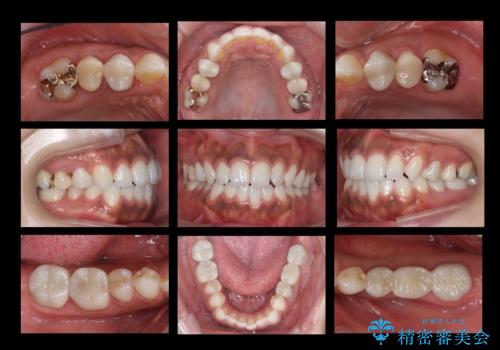

[ 再生治療・歯周外科・小矯正・セラミック補綴 ] 前歯の歯周病治療

担当医 大元洋佑